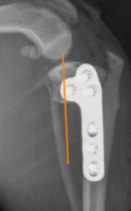

- In both CBLO and TPLO surgeries, a cut is made in the tibia. With a CBLO, the center of force that is placed on the stifle is positioned so that it is directly over the center of the tibia.(see image below). Conversely, the TPLO can cause the center of force to be over the posterior (back) aspect of the bone. In extreme cases, the center of weight can even be behind the bone. This often referred to as a “balcony effect”. This causes a functional limb deformity and can significantly alter the mechanics of the joint. (see image below)

An example of “balcony effect”, where the center of weight (orange line) is well behind the center of the bone.

(Images complements of Hulse 2017)